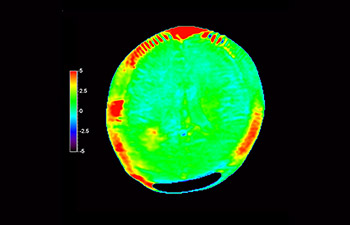

z użyciem metody 3D APT